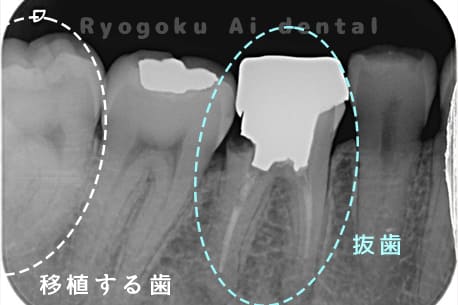

他院で右下の根の治療を行い、セラミックを被せる説明をされていたが、根の治療が終わらないため転院された患者さんです。隣の親知らずの抜歯の必要性と、根の治療を行なっている歯牙の予後が悪いため、移植治療を提案し、右下の親知らずの抜歯と同時に、右下の奥歯(7番)への移植治療を行いました。被せ物を行う必要もなく、順調に経過してます。